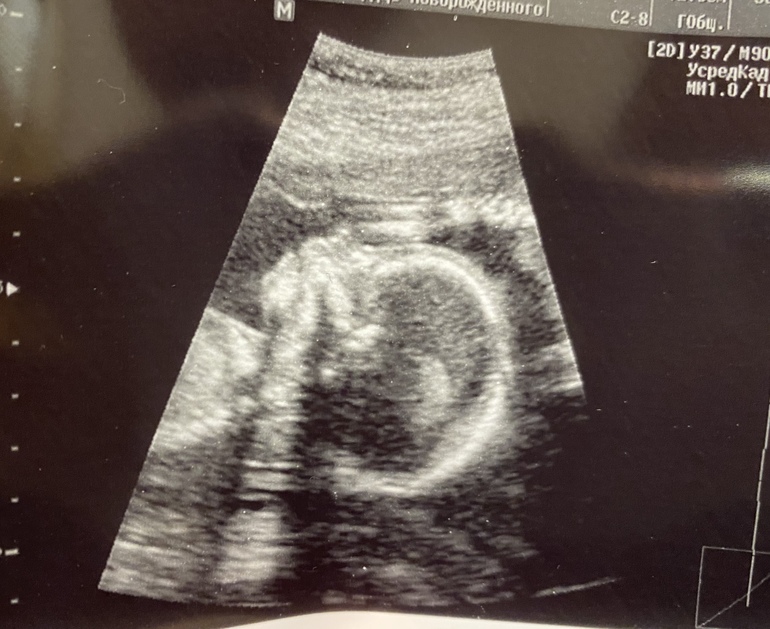

Второй скрининг , срок 19+1

УЗИ, КТГ, доплерДаже не верится!!! Прошли мы второй скрининг😌 Подтвердили нам девочку 🥰 Мы счастливы с мужем))) Заказали ещё неделю назад гендерный тортик. Рады, что не придётся менять цвет начинки))

Малышка соответствует сроку. Это особенно приятно, учитывая, что в 7 недель мы отставали на неделю, еле был заметен эмбрион ( 2.6мм). Столько нервов было потрачено. Хороший урок на будущее нам, девочки, не бежать рано на узи.

Малышка во всю пинается с 16 недель. С каждой неделей сильнее. Есть чем, мы уже 268г😌 Живот мой только ещё не пойми где 🤷🏼♀️ Хочется, чтобы в метро место уступали 😄 тяжело уже через весь город стоя ехать 🤪 Ну хоть впереди неделя отпуска на природе.

Такой симпатичный курносик на фото) поздравляю!)